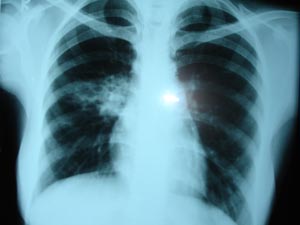

Bronchiectasis

It is an irreversible dilatation of the bronchi. Radiological features includes, Visibly dilated bronchi (tubular or ring shadows), persistent consolidation & loss of volume ( partial collapse ).